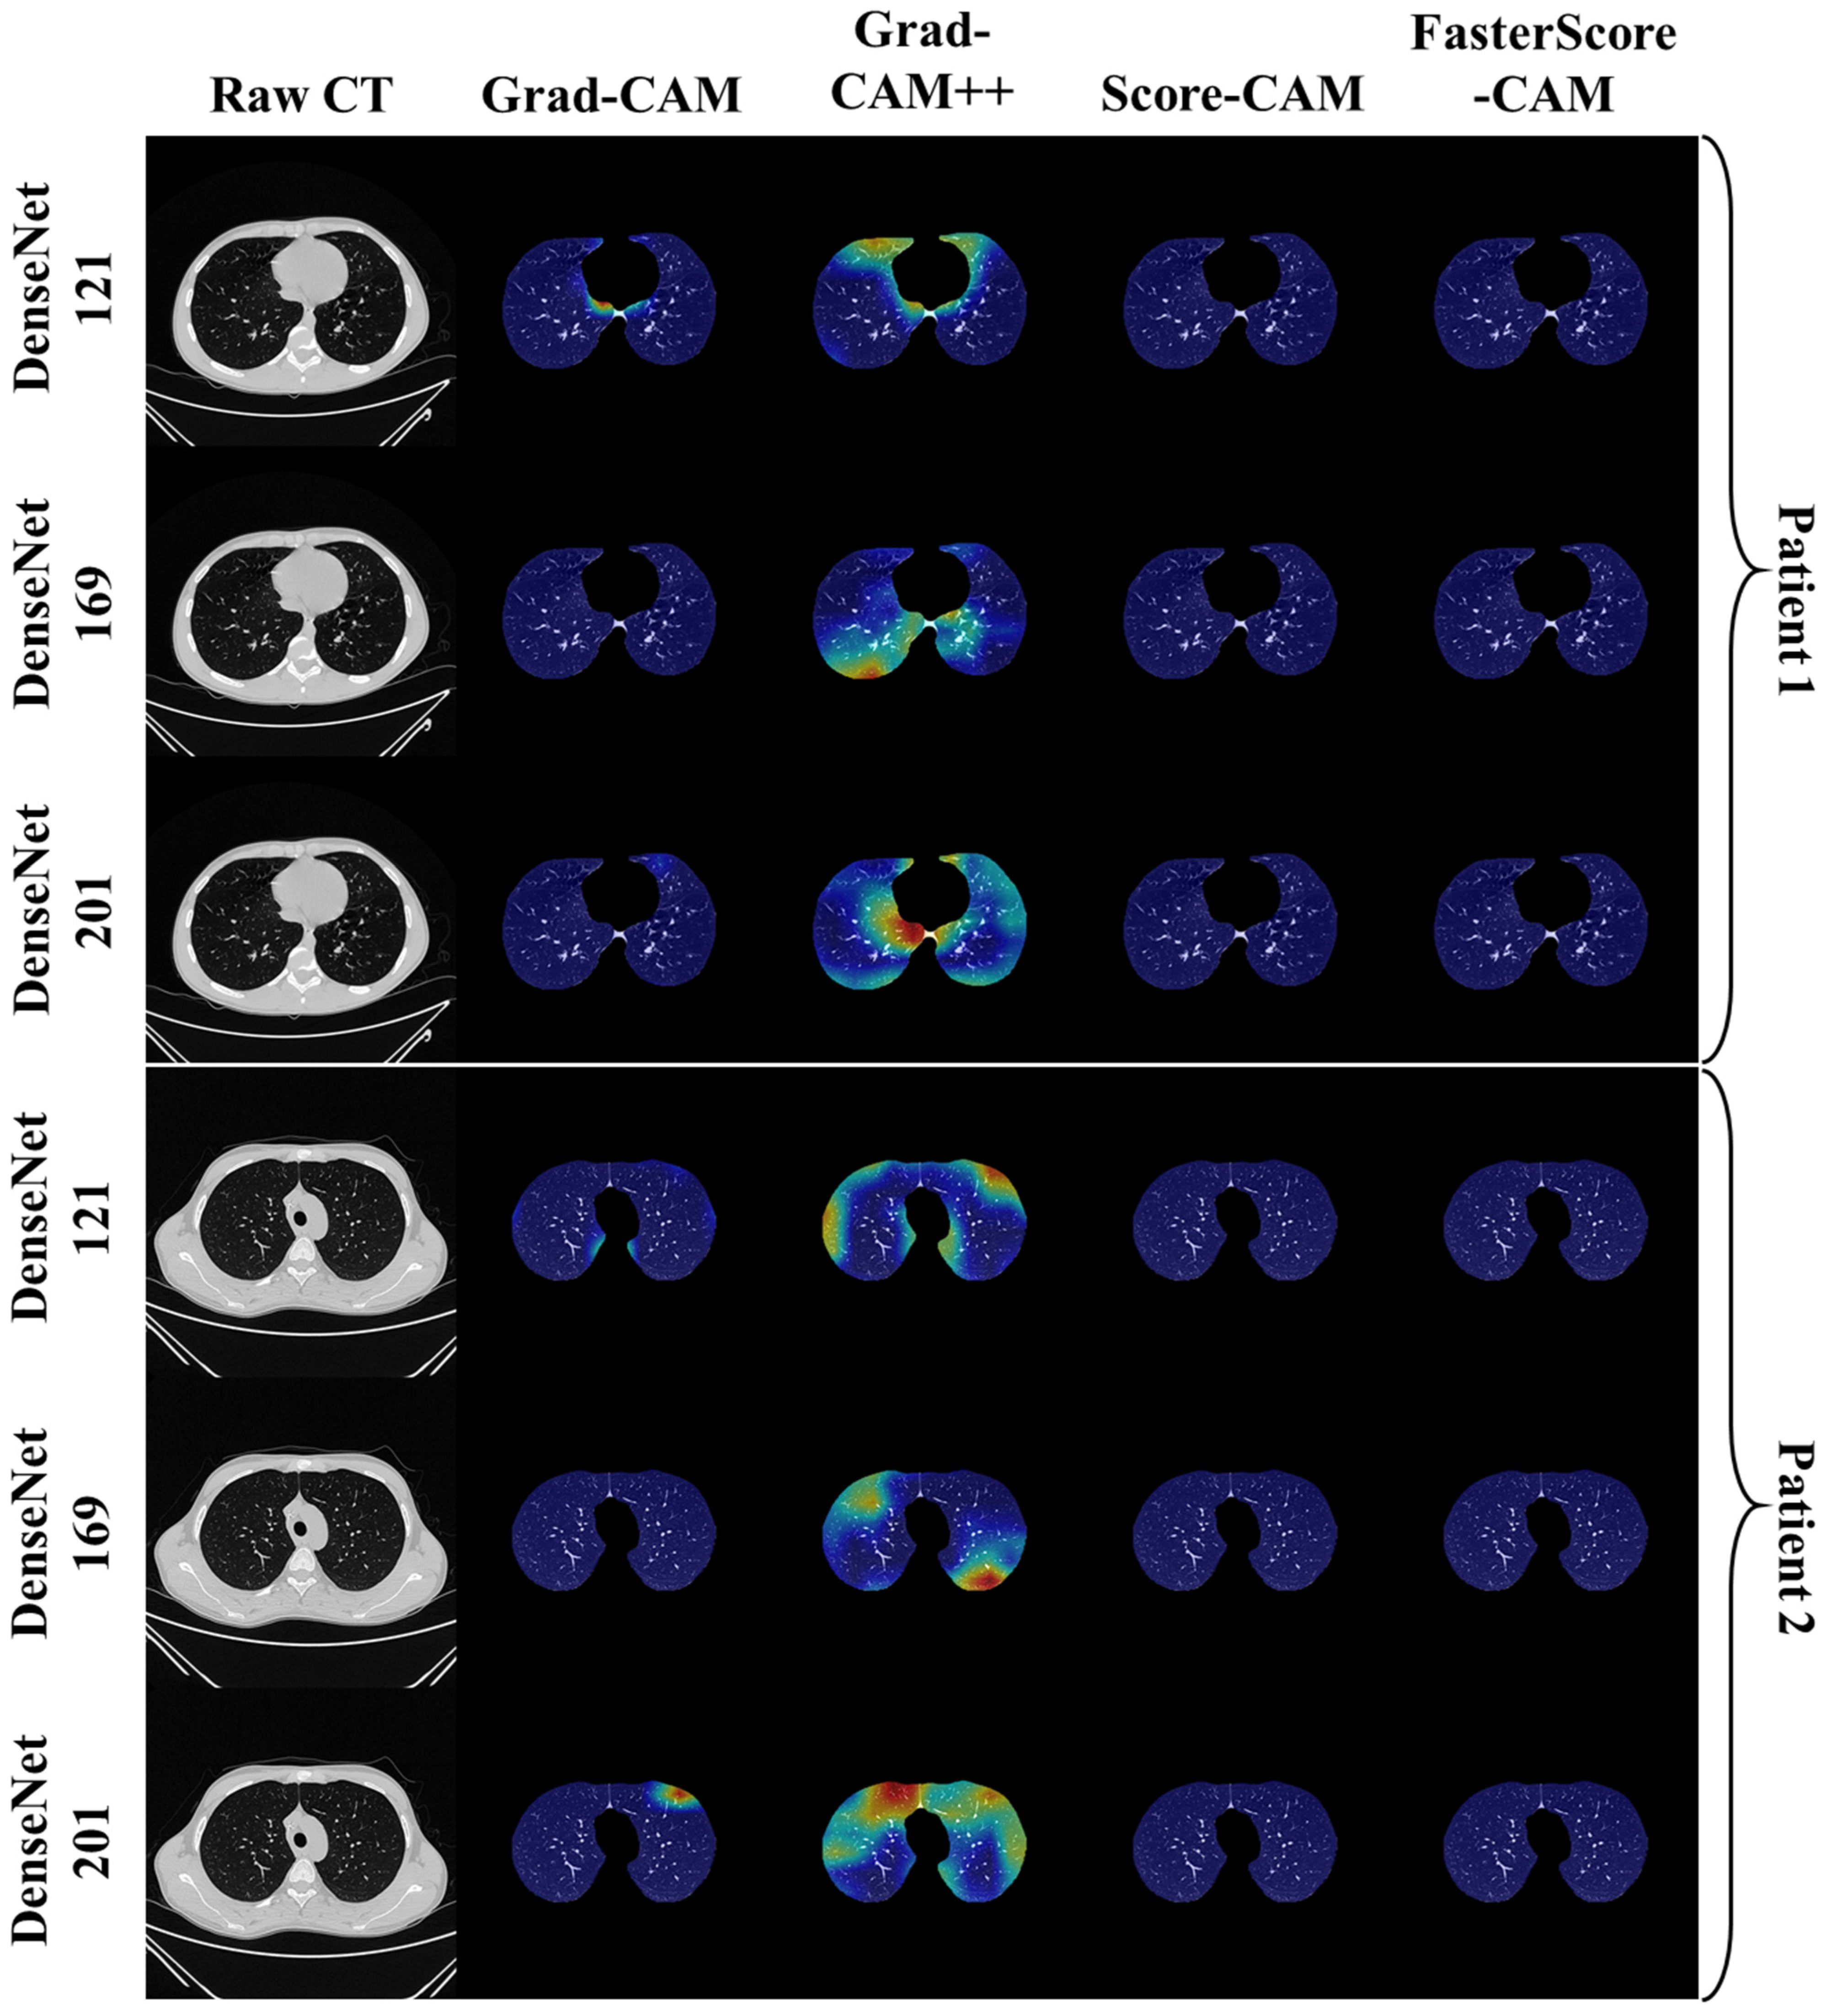

Visual Results Representing Lesion Using the Four CAM Techniques